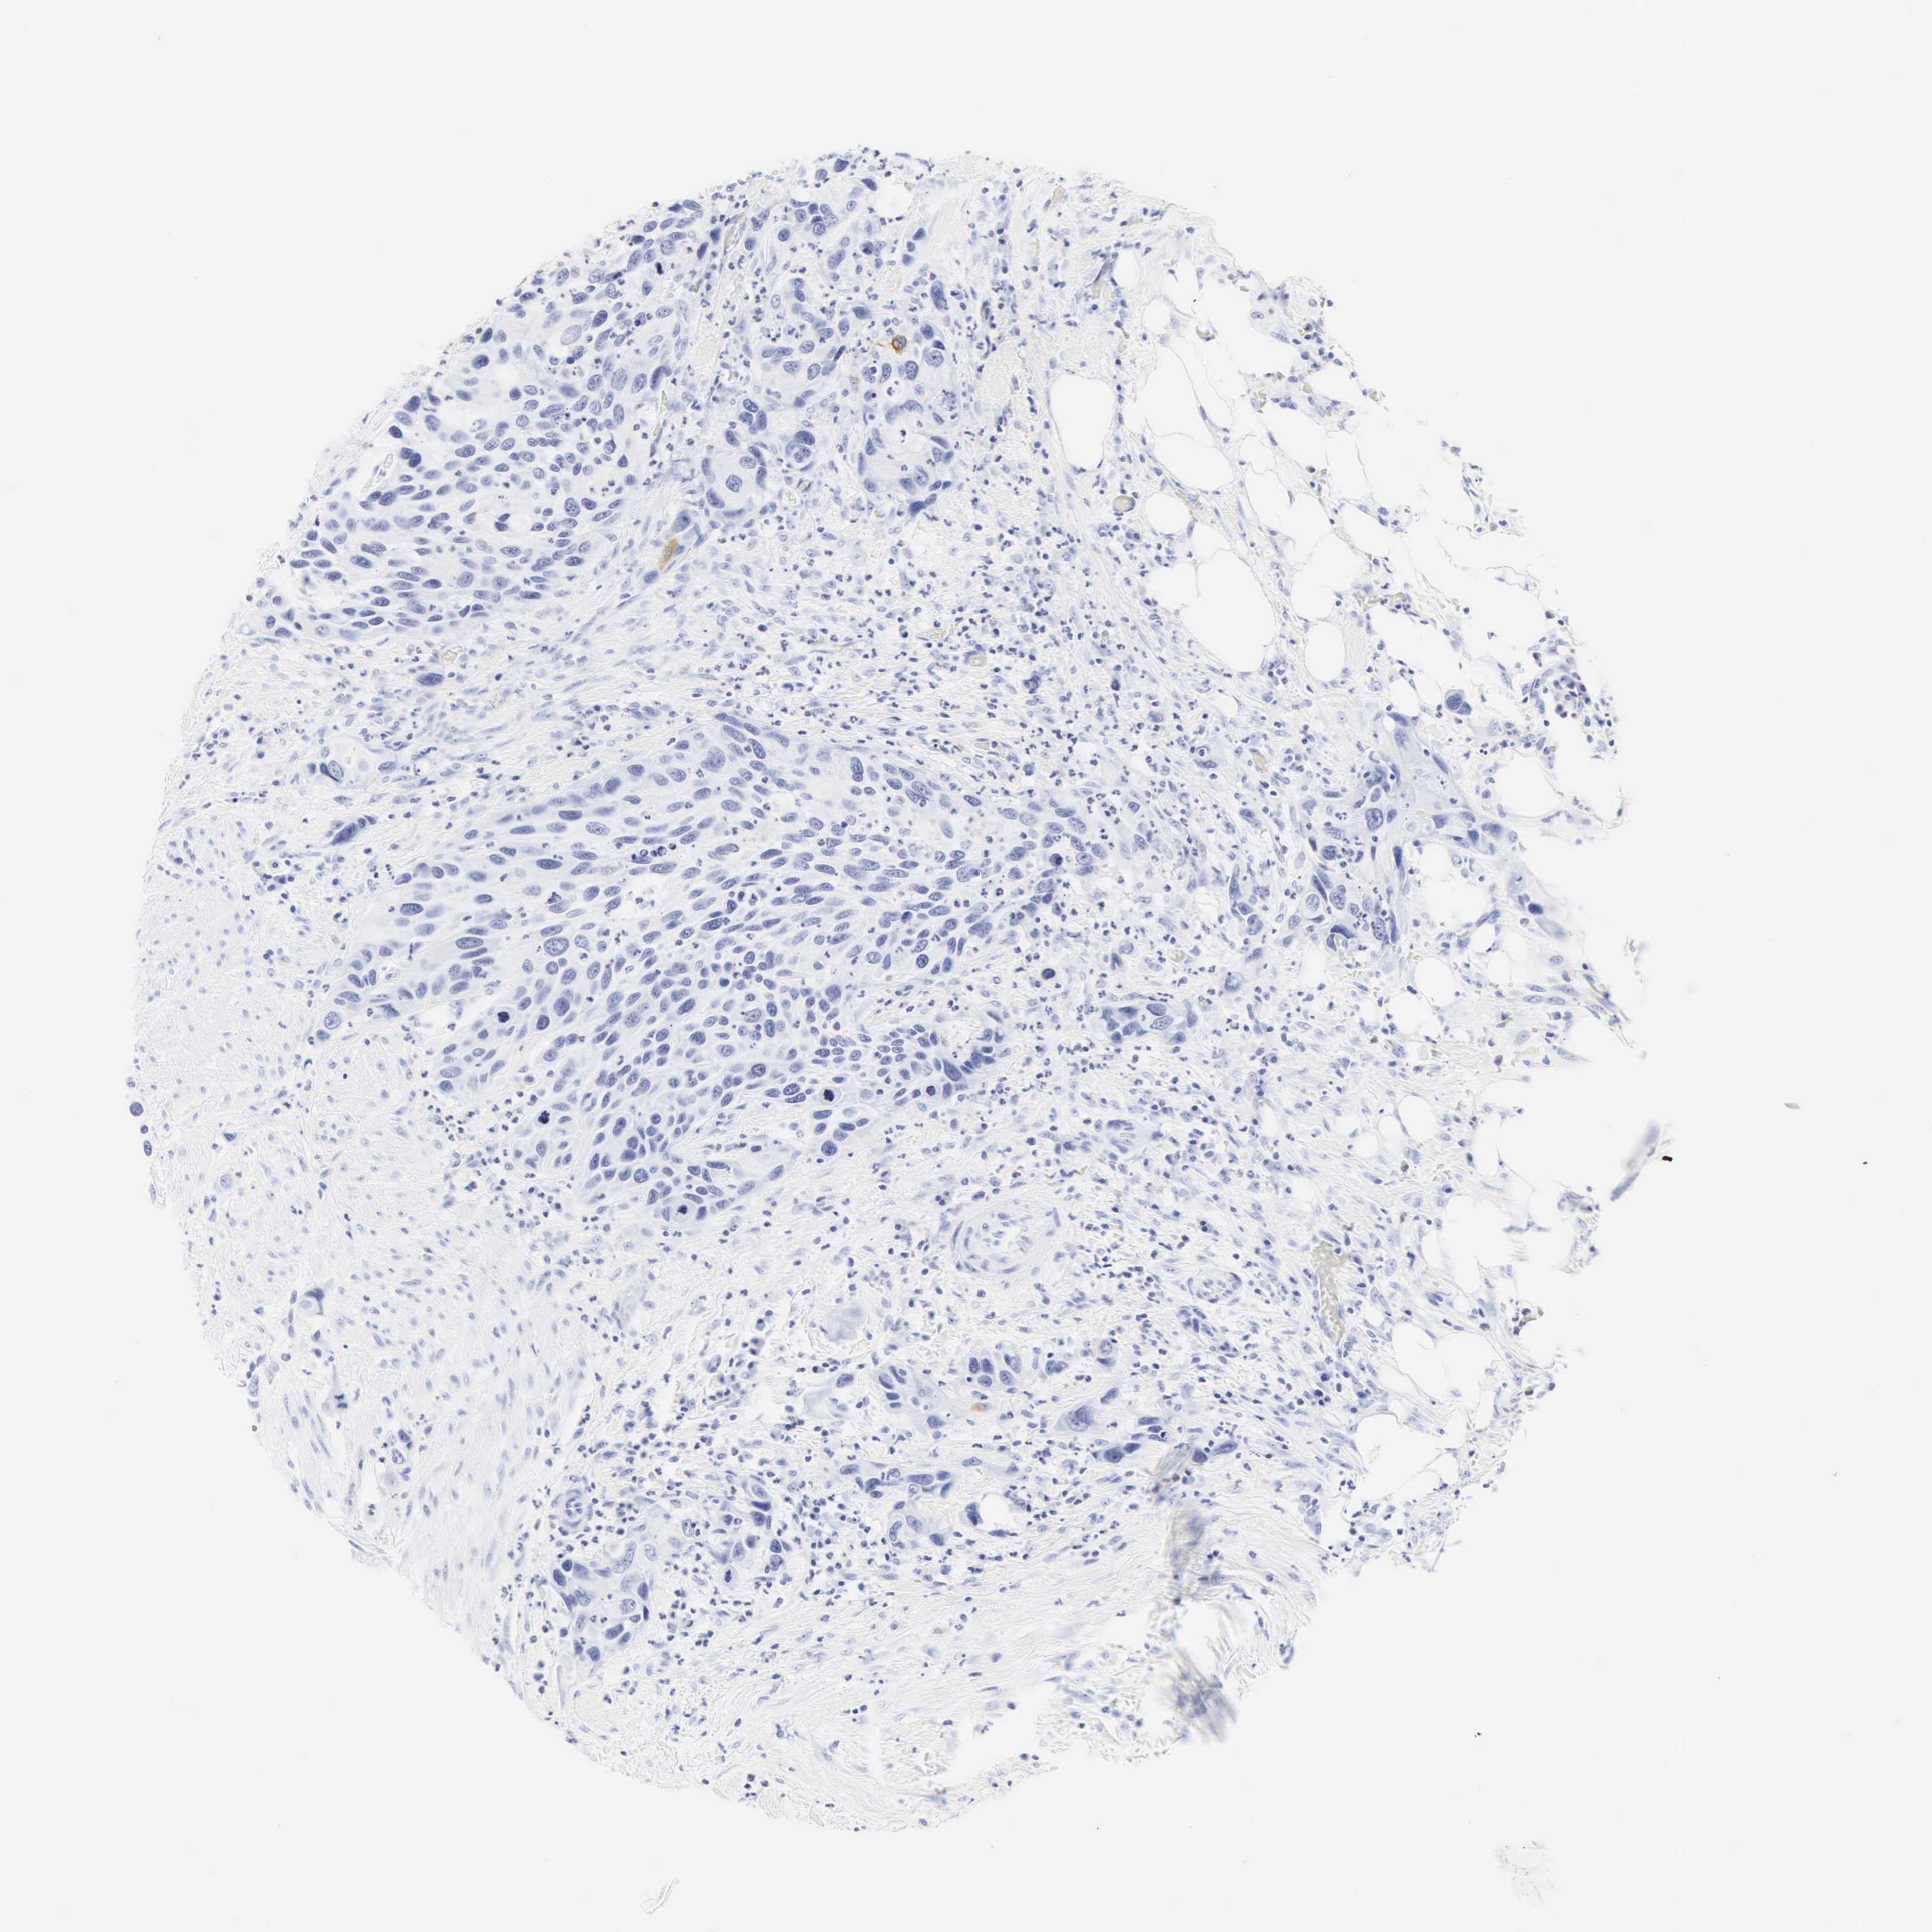

UROTHELIAL CANCER - Protein expressioni

A mouse-over function shows sample information and annotation data. Click on an image to view it in a full screen mode. Samples can be filtered based on level of antibody staining by selecting one or several of the following categories: high, medium, low and not detected. The assay and annotation is described here.

Note that samples used for immunohistochemistry by the Human Protein Atlas do not correspond to samples in the TCGA dataset.

Antibody stainingi

Antibody staining in the annotated cell types in the current human tissue is reported as not detected, low, medium, or high, based on conventional immunohistochemistry profiling in selected tissues. This score is based on the combination of the staining intensity and fraction of stained cells.

Each image is clickable and will lead to virtual microscopy that enables deeper exploration of all samples and also displays staining intensity scores, fraction scores and subcellular localization as well as patient and tissue information for each sample.

Antibody HPA038925

Antibody HPA038934

Antibody CAB000042

Antibody CAB010884

Staining

High

Medium

Low

Not detected

Intensity

Strong

Moderate

Weak

Negative

Quantity

>75%

75%-25%

<25%

None

Location

Nuclear

Cytoplasmic/membranous

Cytoplasmic/membranous,nuclear

Urothelial carcinoma, High grade

Urothelial carcinoma, Low grade

Adenocarcinoma, NOS